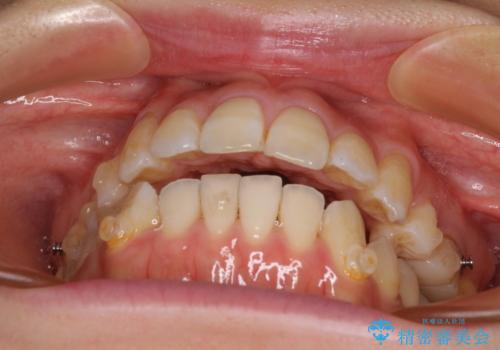

八重歯と開咬の抜歯矯正 ワイヤー装置を併用したインビザライン矯正治療

- 咬み合わない前歯と八重歯などのデコボコを気にして来院された患者様です。

上下前歯の位置を比較すると上顎が前方にあり、デコボコ改善でより上顎が前方に行く可能性があります。

開咬の改善にはインビザラインが有効であり、インビザライン単体での治療を検討しましたが、上顎前突を回避するために上顎左側第一小臼歯抜歯を行うこととしたため、補助装置とワイヤー矯正を併用した上で、インビザラインによる矯正治療を行うこととしました。

インビザライン矯正治療では、臼歯の圧下による前歯部の早期接触が大きな問題となっています。開咬では、その臼歯圧下を逆手にとって前歯部の非接触を改善させることができます。